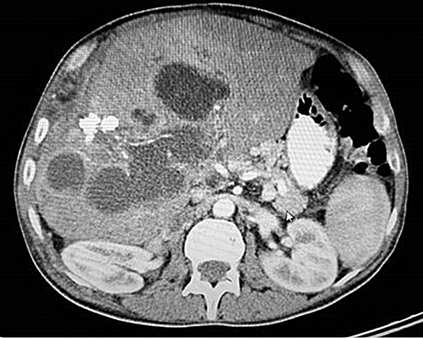

A 53 year old male patient presented with severe abdominal pain. The patient had been operated 3 times for liver hydatid cyst due to Echinococcus granulosus. The ultrasonography demonstrated no portal blood flow and portal vein thrombosis was detected. There were vesicular cystic lesions inside the portal vein. Dynamic computerized tomography of the liver revealed lesions initiating from periportal region and extending to both liver lobes, which were associated with the hydatid cyst (Figure 1).

Moreover, the thrombus of echinococcus was extending until the lumen of superior mesenteric vein.

There were numerous hydatid cysts in the liver. There were a lot of portal collaterals in the portal hilus because of the hydatid thrombus inside the portal vein. Right and mid hepatic veins could not be visualized due to the thrombosis.

Figure 1. CT scan